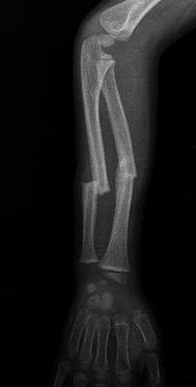

ÖN KOL ÇİFT KIRIĞI

Doktor Mehmet Subaşı

Ön-kol kemiğini oluşturan Radius ve ulna kemiklerinin ikisinin bera...